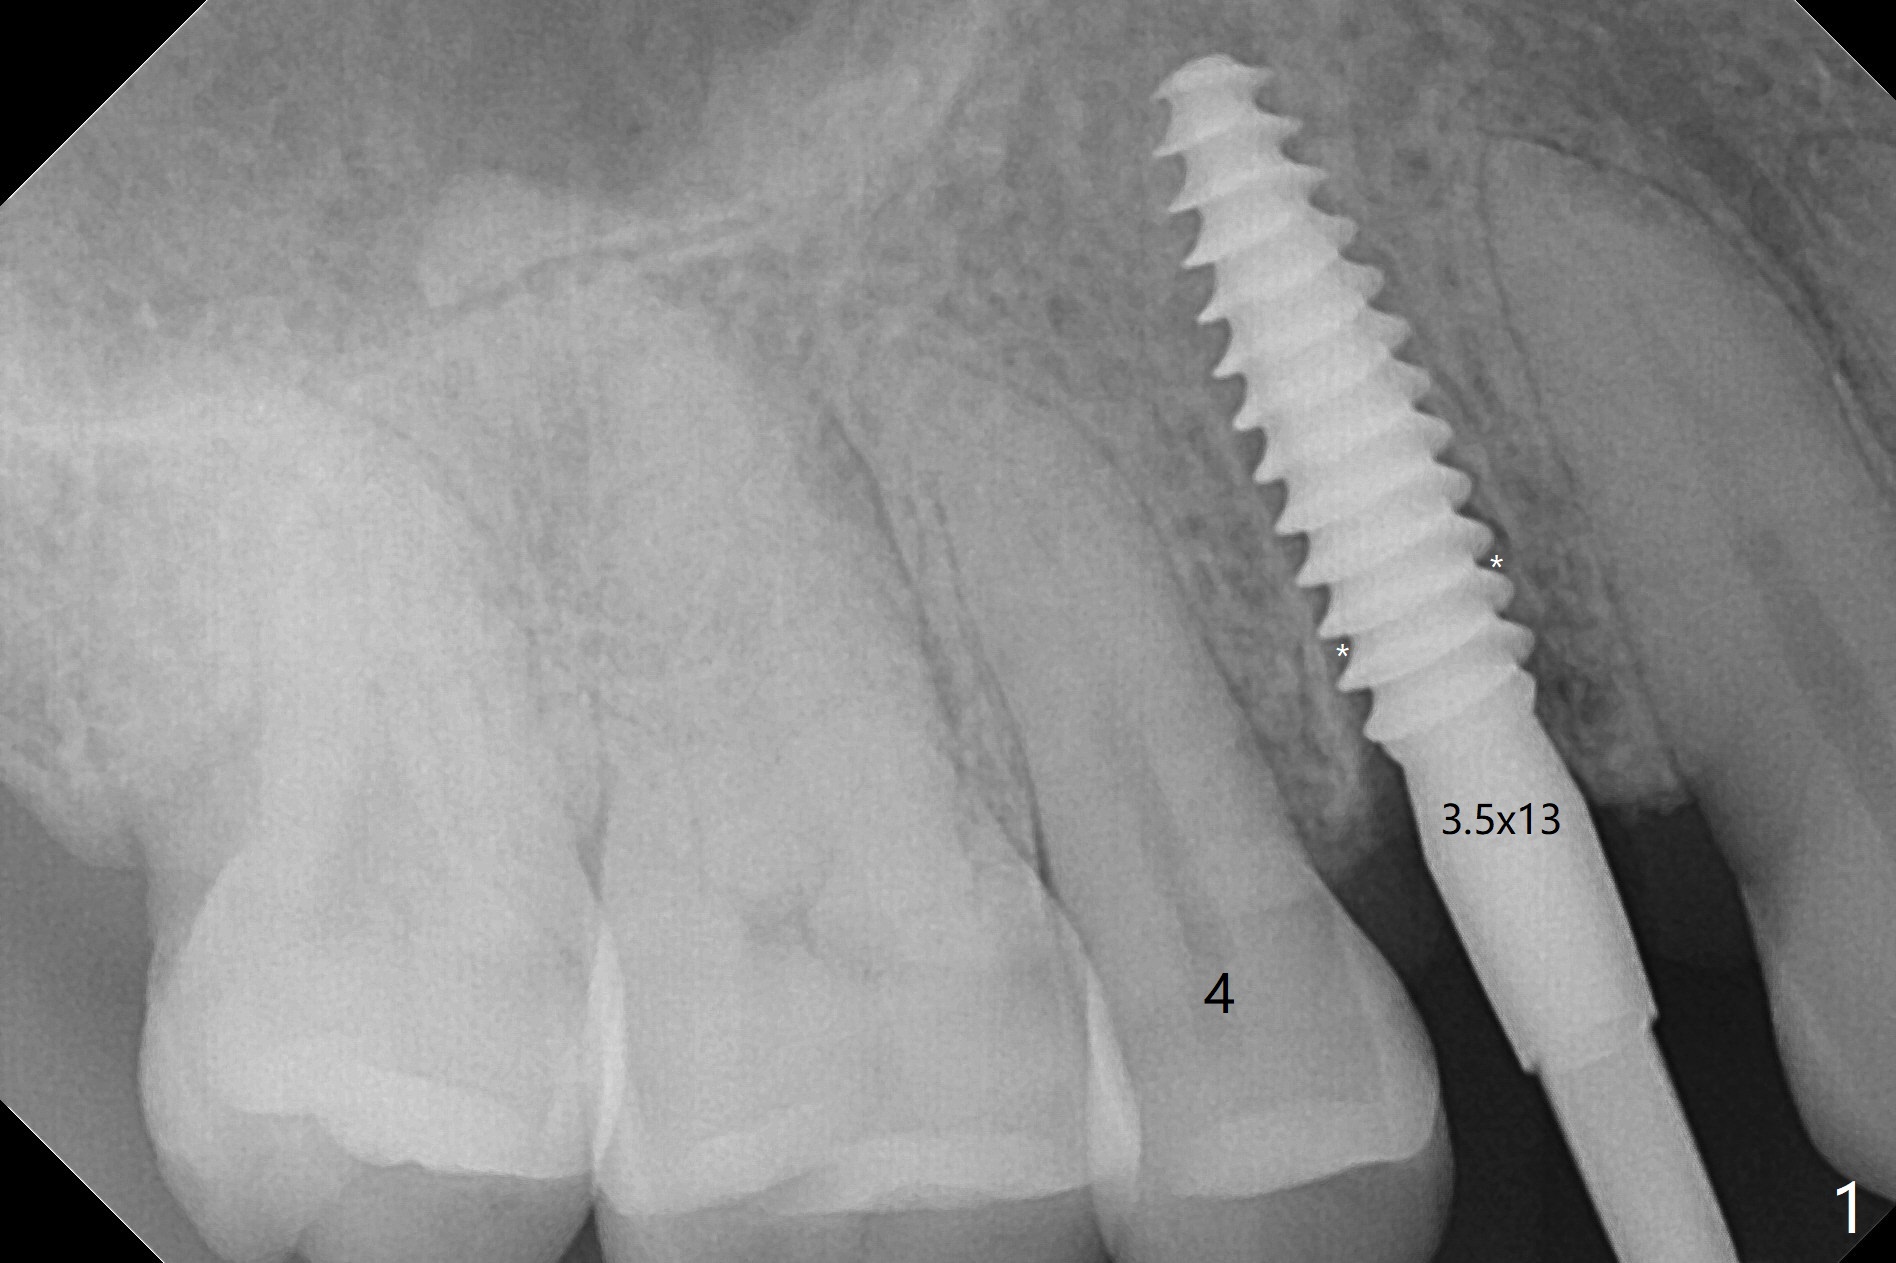

拔除根管治疗后第一双尖牙,花费不少时间(牙根松软,最后需要劈开),但是使用导板,植入一段式植体显得利索,不要花时间正确放置基台,而且植体冠部不仅没有与颊侧,舌侧骨板接触,而且与近中,远中牙槽嵴有一定空间(图一:*)对牙槽嵴没有压力,减少术后骨质吸收。降低基台高度后(图二:箭头),用骨粉充填(图二:*)。